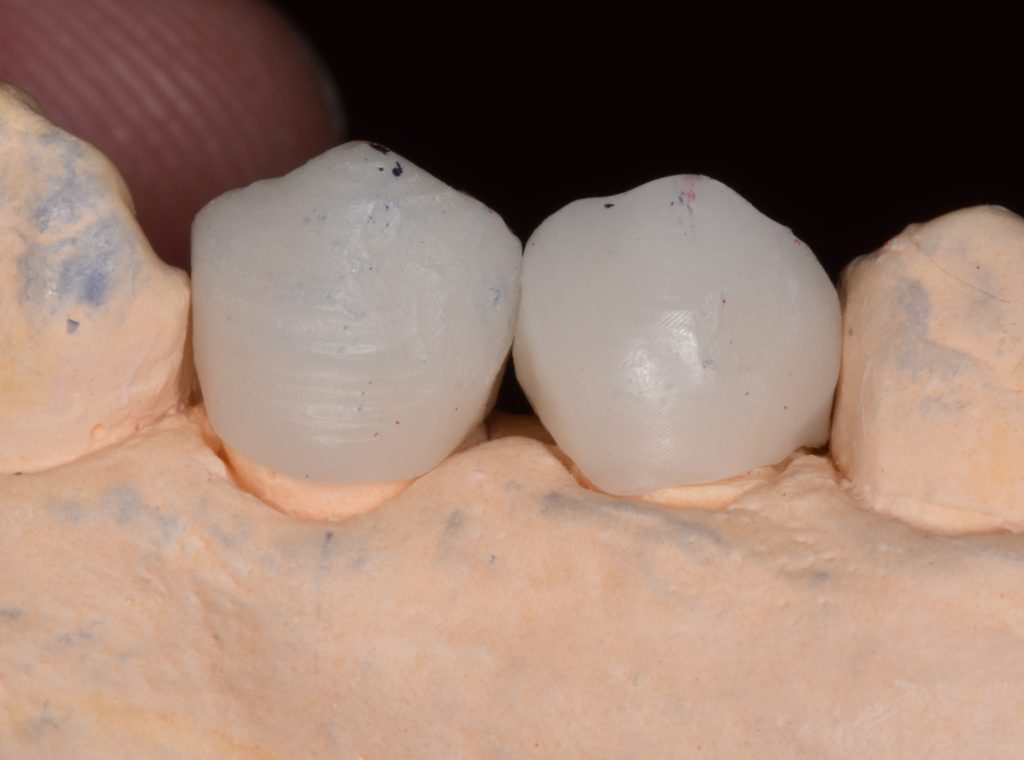

I decided to go for indirect lithium disilicate restorations

And final design to receive to monolithic lithium disilicate restorations